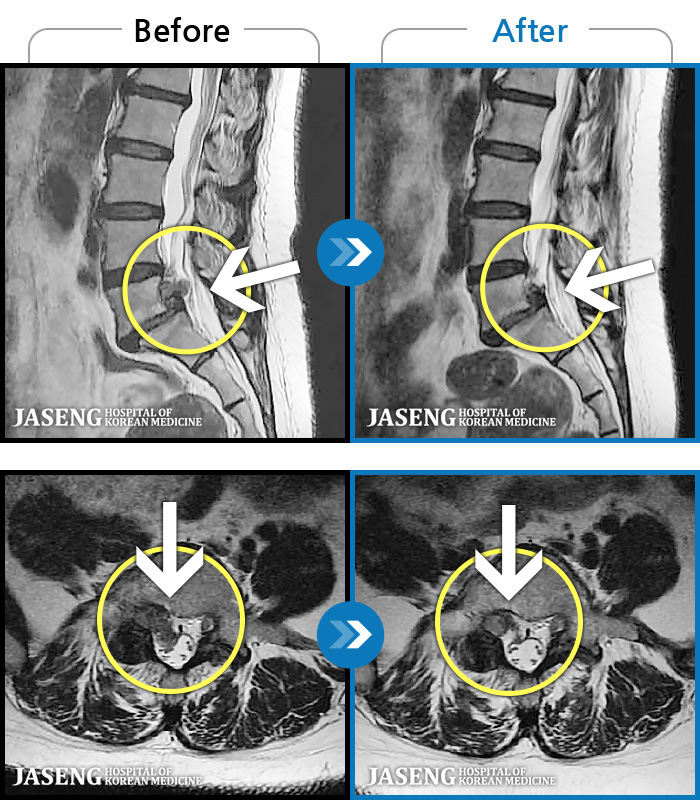

MRI ġ

1,240 MRI ũ ʸ Ȯϼ.